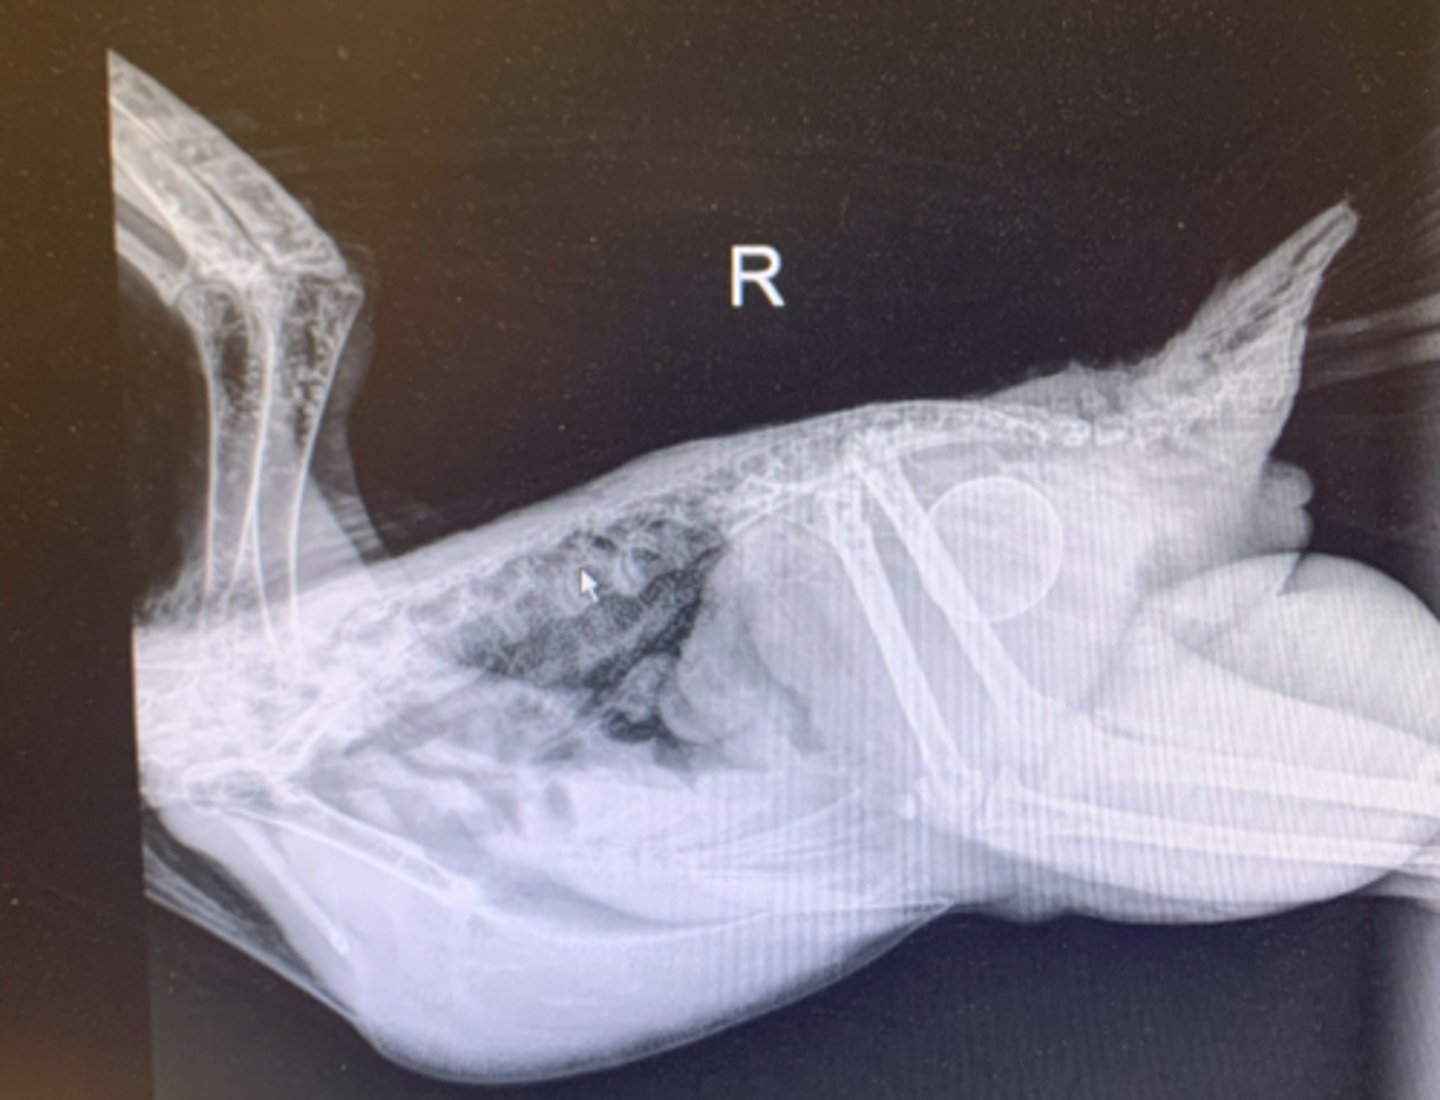

1. small egg

2. hernia = must do barium study to determine if repro. or digestive organs or inside

Describe some things you see in this bird

Metal opacities - lead pellets are a good differential for toxicity causing seizures in birds, zinc would be too

TREAT: CaEDTA to decontamination

A 4 month old peahen is presenting with seizures and you get this radiograph. What do you see and what can you do?